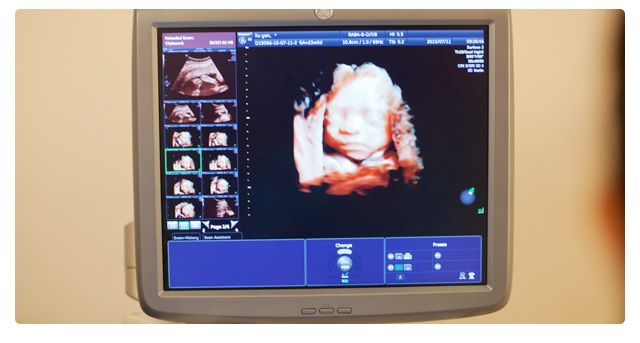

四維彩超對胎兒的體表進行檢查,如唇裂,脊柱裂,大腦、腎、心臟、骨骼發(fā)育不良等,以便盡早的進行治療。四維彩超還觀察運動神經系統(tǒng)是否正常,運動是否協調。四維彩超的檢查時間是懷孕22周-26周。選擇安琪兒做排畸,孕媽更放心,立即在線咨詢詳情

系統(tǒng)B超和四維彩超最大的區(qū)別就是一個“時間維”的問題,簡單的說,系統(tǒng)B超是圖片,是靜態(tài)的;而四維彩超是錄像,是動態(tài)的,可以讓孕媽媽看到胎兒一連串的動作。因此,四維彩超看起來會更加清晰,系統(tǒng)B超只是在某個時間點上的照片。

其次,系統(tǒng)B超和四維彩超同樣都有排畸的作用,系統(tǒng)B超側重觀察五臟六腑是否畸形,排除結構畸形;而四維彩超能夠多方位、多角度地觀察宮內胎兒的生長發(fā)育情況,為早期診斷胎兒先天性體表畸形和先天性心臟疾病提供更加有效的科學依據。

1.高精尖設備:采用美國GE E8四維彩超排畸,血細胞放大1000倍,4D清晰成像,輻射僅為手機輻射的萬分之一。